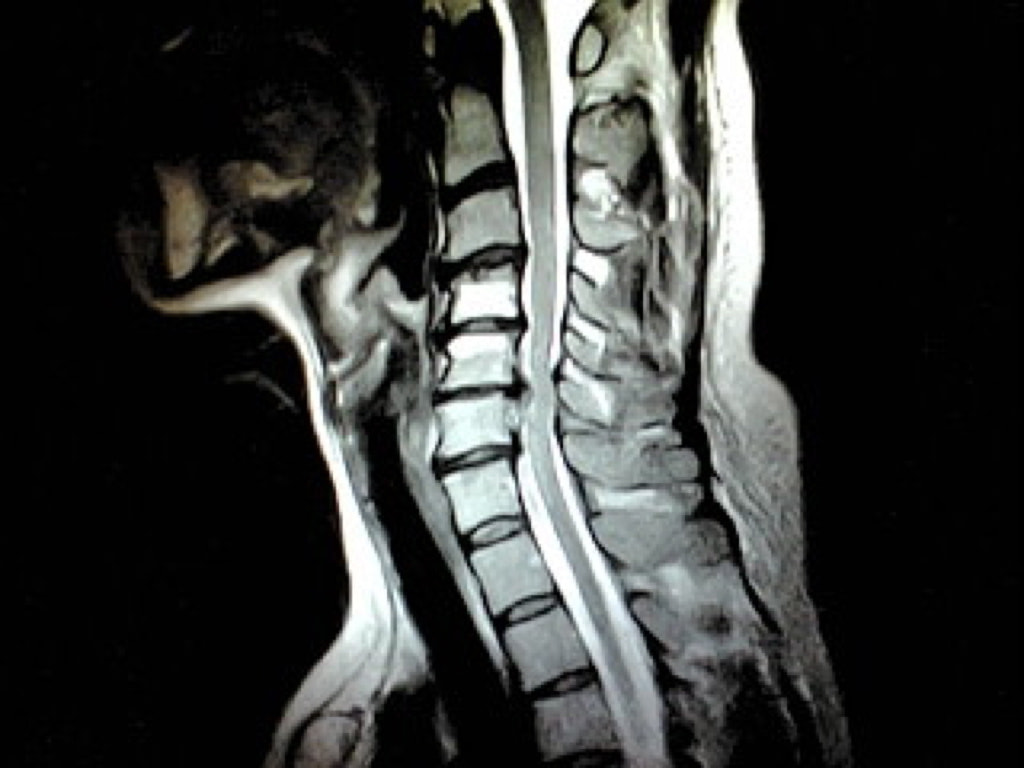

頚椎MRI画像

4|頚椎MRIドック

頸部痛や手のしびれの原因となる頸椎椎間板ヘルニアや頸部脊柱管狭窄症などが発生する頸椎を無痛でチェックします。

所要時間:30分  費用:22000円(消費税込み)